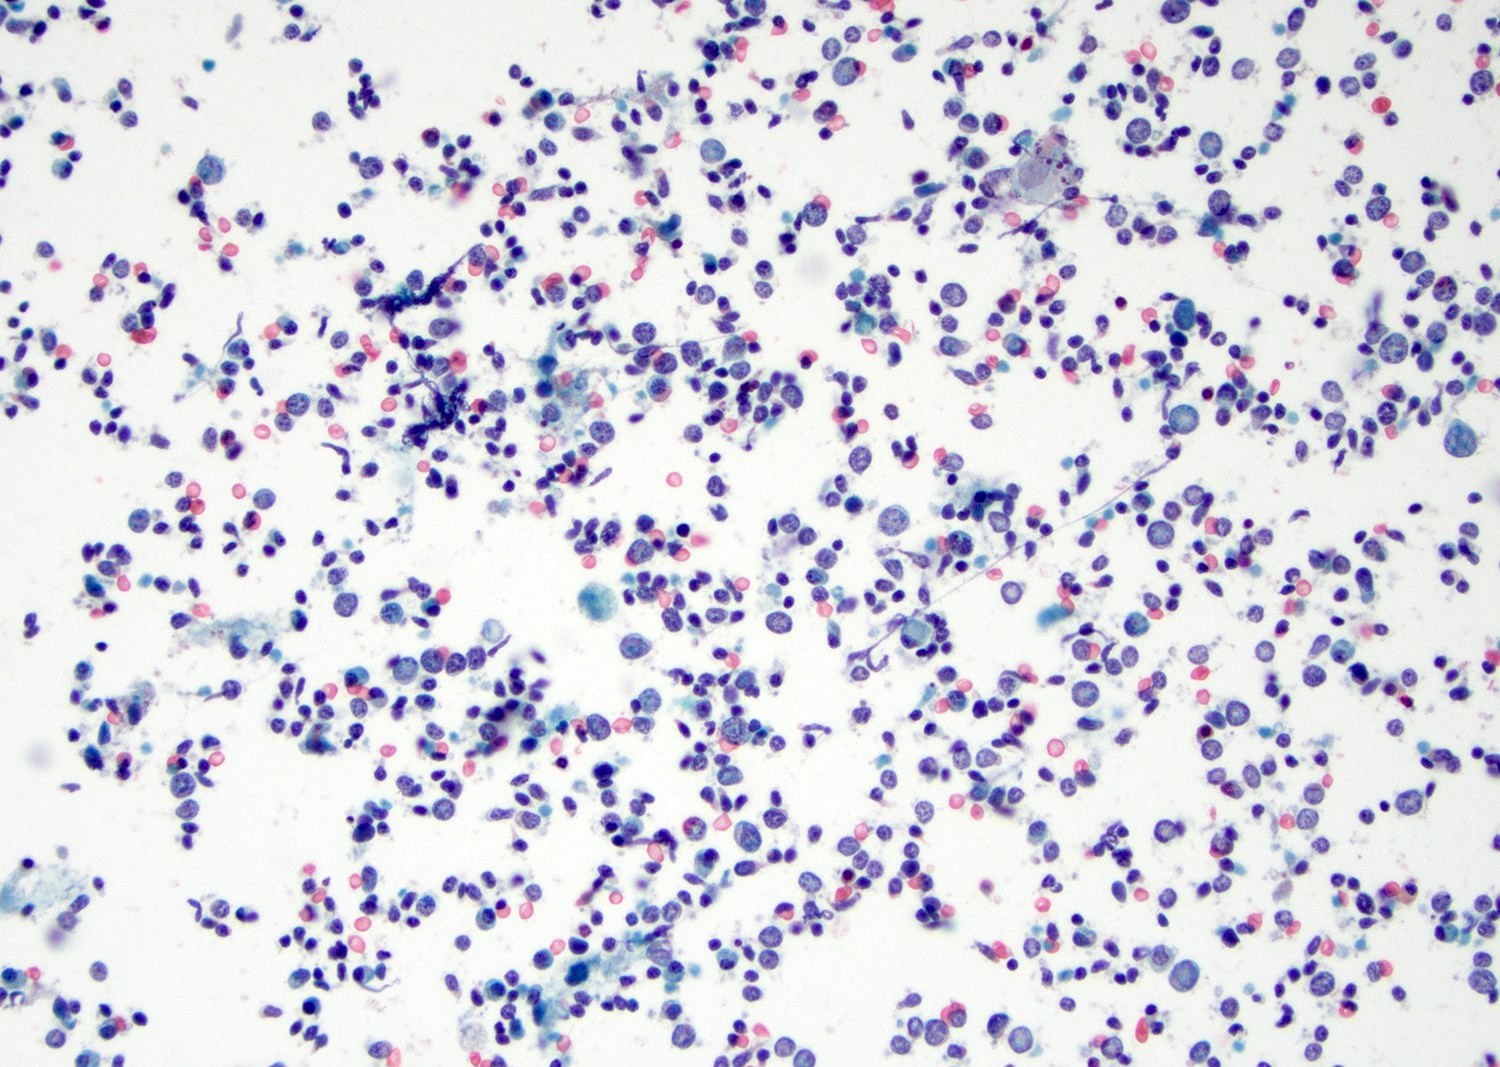

Cytology description

- Mature nucleated squamous cells with variable reactive atypia, anuclear cells and squamous epithelium (Int J Surg Case Rep 2017;41:383, Diagn Cytopathol 2012;40:684)

- Polymorphous lymphocytes and aggregates of epithelioid histiocytes

- Proteinaceous background

- Variable presence of acute inflammation, and bland appearing mucinous ductal cells and ciliated columnar cells

- Scant cellularity, abundant proteinaceous background, lack of squamous cells and epithelial cells, marked atypia of epithelial cells, abundance of lymphocytes pose diagnostic challenges

Cytology images